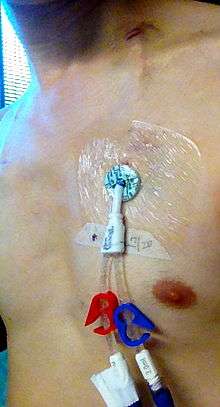

Non-tunneled vs. tunneled catheters

Non-tunneled catheters are fixed in place at the site of insertion, with the catheter and attachments protruding directly. Commonly used non-tunneled catheters include Quinton catheters.

Tunneled catheters are passed under the skin from the insertion site to a separate exit site. The catheter and its attachments emerge from underneath the skin. The exit site is typically located in the chest, making the access ports less visible than catheters that protrude directly from the neck. Passing the catheter under the skin helps to prevent infection and provides stability. Commonly used tunneled catheters include Hickman catheters and Groshong catheters.

Depending on use, catheters may have a single lumen (a "monoluminal catheter") or multiple lumens. A catheter with two lumens is "biluminal", three "triluminal". Up to 4 or 5 lumens may be used, allowing multiple drug infusions to be delivered and monitored simultaneously.

The catheter is held in place by an adhesive dressing, suture, or staple which is covered by an occlusive dressing. Regular flushing with saline or a heparin-containing solution keeps the line open and prevents blood clots. There is no evidence that heparin is better than saline at preventing blood clots.[24] Certain lines are impregnated with antibiotics, silver-containing substances (specifically silver sulfadiazine) and/or chlorhexidine to reduce infection risk.[25]